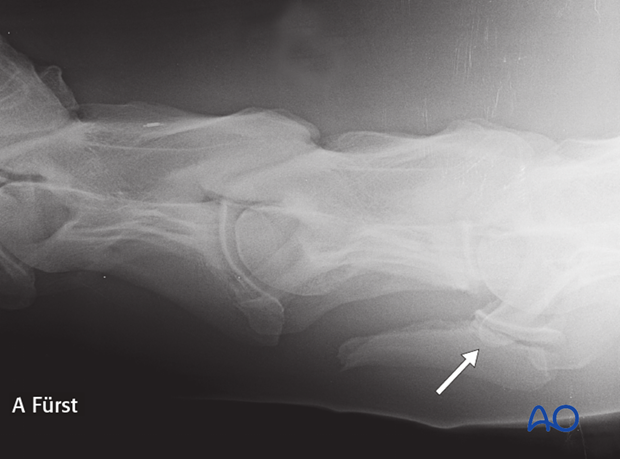

Radiographs:

Radiographic examination: